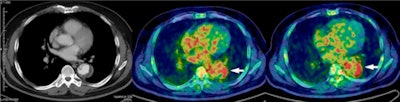

| Above: Enhanced CT (left) shows acute aortic dissection consistent with low uptake of FDG in intramural hematoma lesion on transaxial PET/CT at 50 minutes (middle) and 100 minutes (right). This 82-year-old woman experienced acute aortic dissection regression two months after onset but had a favorable outcome. Below: Enhanced CT (left) shows acute aortic dissection consistent with high uptake of FDG in dissected aortic wall on transaxial PET/CT at 50 minutes (middle) and 100 minutes (right). This 44-year-old man underwent elective repair of aortic aneurysm because of acute aortic dissection progression three months after onset and experienced an unfavorable outcome. Images courtesy of JNM. |